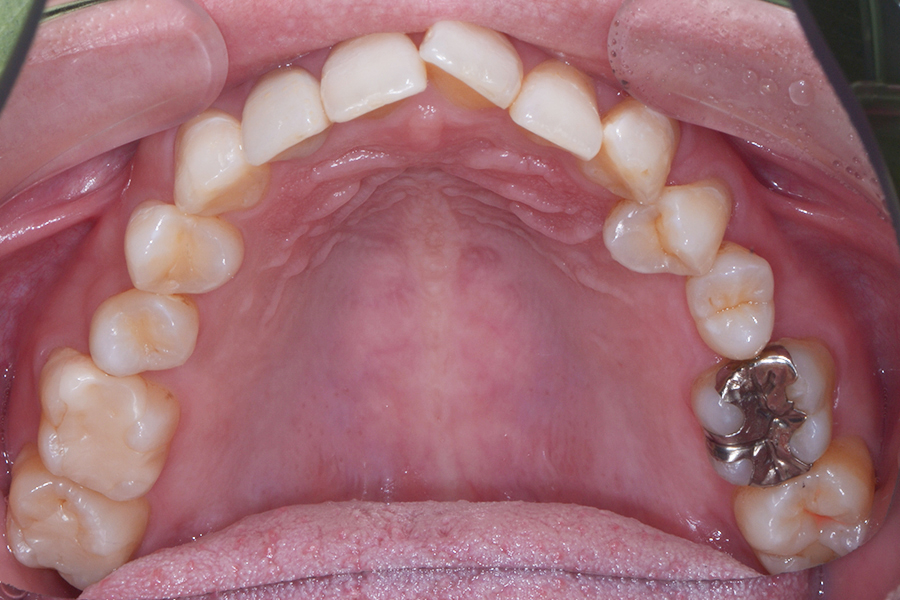

【20代女性】一本だけ引っ込んでいる。

ねじれも治したい

【矯正歯科治療】

- 担当医

- 三留先生

- 主訴

- 一本だけ引っ込んでいる。ねじれも治したい

- 期間

- 12か月

- 費用

- 治療費35万+35万(別途調整料)

- 治療内容

- 上下顎リンガル矯正(裏側矯正)

- 治療に伴うリスク

- 後戻り